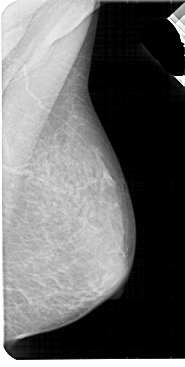

A_1947_1.RIGHT_MLO

RIGHT_MLO LINES 5491 PIXELS_PER_LINE 2761 BITS_PER_PIXEL 12 RESOLUTION 43.5 NON_OVERLAY